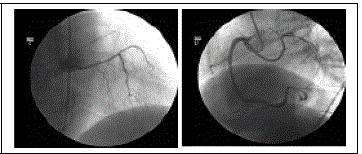

As imagens abaixo são de um paciente com diagnóstico anatômico de origem anômala independente das artérias descendente anterior (DA) e circunflexa (Cx) em torno do óstio da coronária direita tópica.

Assinale a alternativa que preenche correta e respectivamente as lacunas da frase abaixo.

Para atingir o septo interventricular anterior, a DA cursa o trajeto .........., e, para atingir o sulco atrioventricular esquerdo, a Cx cursa o trajeto .......... .